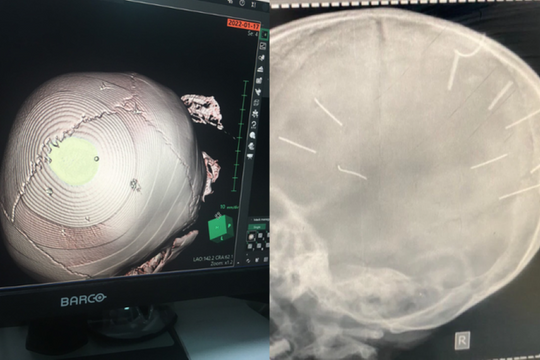

PLBĐ - Vụ bé gái 3 tuổi ở Hà Nội được đưa vào viện cấp cứu trong tình trạng hôn mê, co giật với 9 dị vật giống đinh ghim ở sọ não đang nhận được nhiều sự quan tâm của dư luận. Hiện, Công an Hà Nội đã chỉ đạo Phòng Cảnh sát hình sự thụ lý điều tra vụ việc.